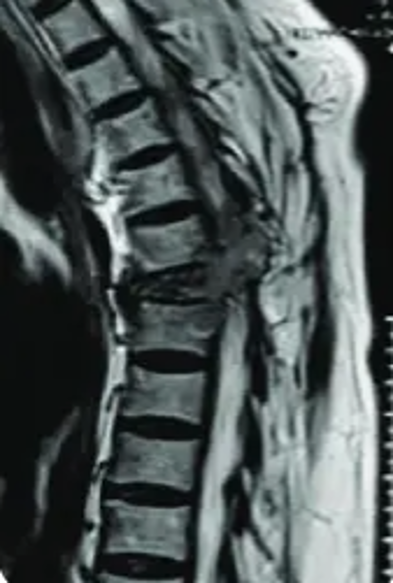

Surgery to remove tumors (benign or cancerous) that grow inside or around the spine.

The tumor is carefully removed while protecting nerves and the spinal cord. Sometimes rods or screws are added for stability.

Tumor Removal

The tumor is carefully removed while protecting nerves and the spinal cord.

Nerve Protection

Advanced neuromonitoring ensures safety throughout the procedure.